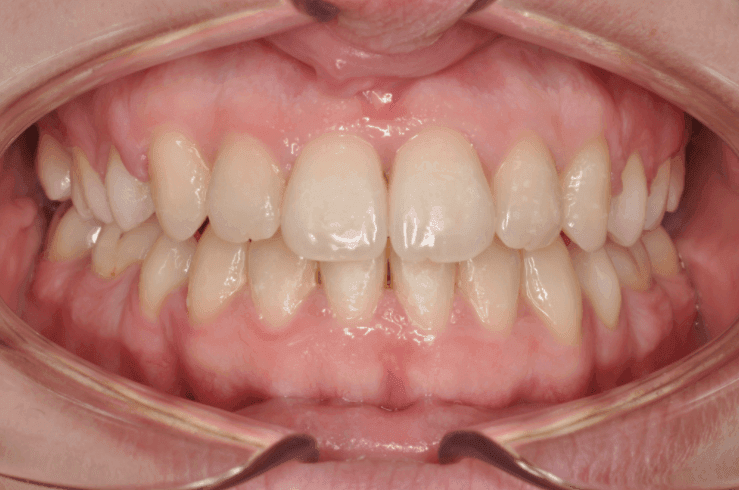

Kako slike obično govore više od reči, na sledećim slikama možete pogledati sjajne rezultate postignute nošenjem fiksnih proteza kod jednog našeg pacijenta: